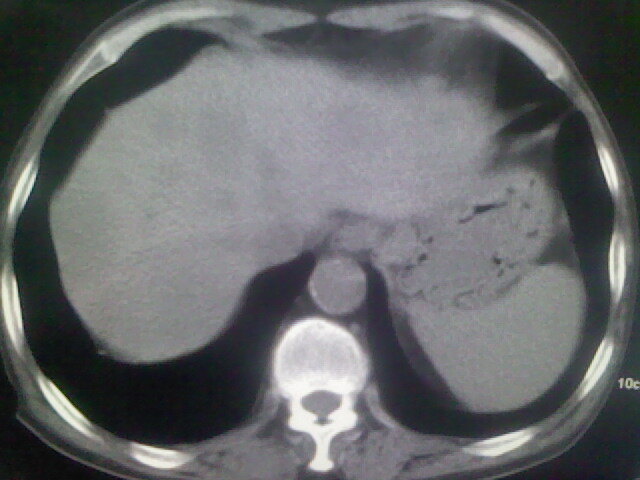

男,70y,胃占位,重度贫血,黑便3月余,伴恶心,纳差,乏力

肝内弥漫低密度---转移瘤

右上肺周围型肺癌,肝内多发低密度影---转移瘤?建议增强;胃壁明显增厚.

考虑右上肺周围型肺癌,肝内多发低密度影考虑转移瘤?建议增强;胃腔充盈欠佳。不好确定。

2、胃充盈欠佳,不能确定。

资料不清晰啊,肺内病灶内可见多发钙化影,结核不能除外.肝内符合转移瘤表现.既然楼主提供胃内占位,那原发灶还是考虑来源于胃腔.